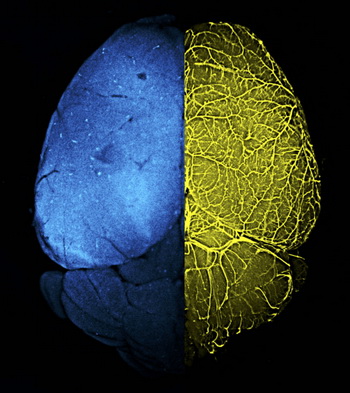

左側(cè):血腦屏障傳統(tǒng)遺傳靶向工具小鼠Mfsd2a-CreER; R26-tdTomato標(biāo)記大腦細(xì)胞熒光圖

右側(cè):器官特異性遺傳靶向工具小鼠BEC-Cre更加精準(zhǔn)地標(biāo)記大腦血管內(nèi)皮細(xì)胞